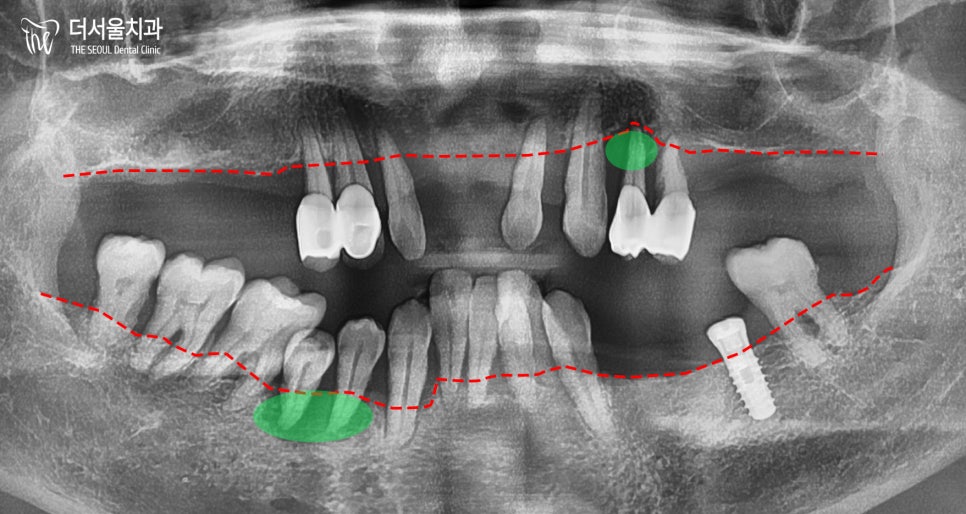

엑스레이로 확인한 결과,

치아가 왜 그렇게 흔들리는지 알 수 있었습니다.

이미 잇몸뼈가 내려 앉을대로

많이 퇴축되었음을 확인할 수 있었는데요.

뿌리 끝만 붙잡고 있는 곳도 있으니

심하게 흔들릴 수밖에 없죠.

또, 곳곳에 큰 염증을 찾아볼 수 있구요.

살릴 수 있는 치아는 정말 소수였습니다.

아래 양쪽 끝 어금니들만 살아남았죠.

36번 임플란트, 37, 46, 47번 어금니를 제외한

모든 치아를 발치했습니다.